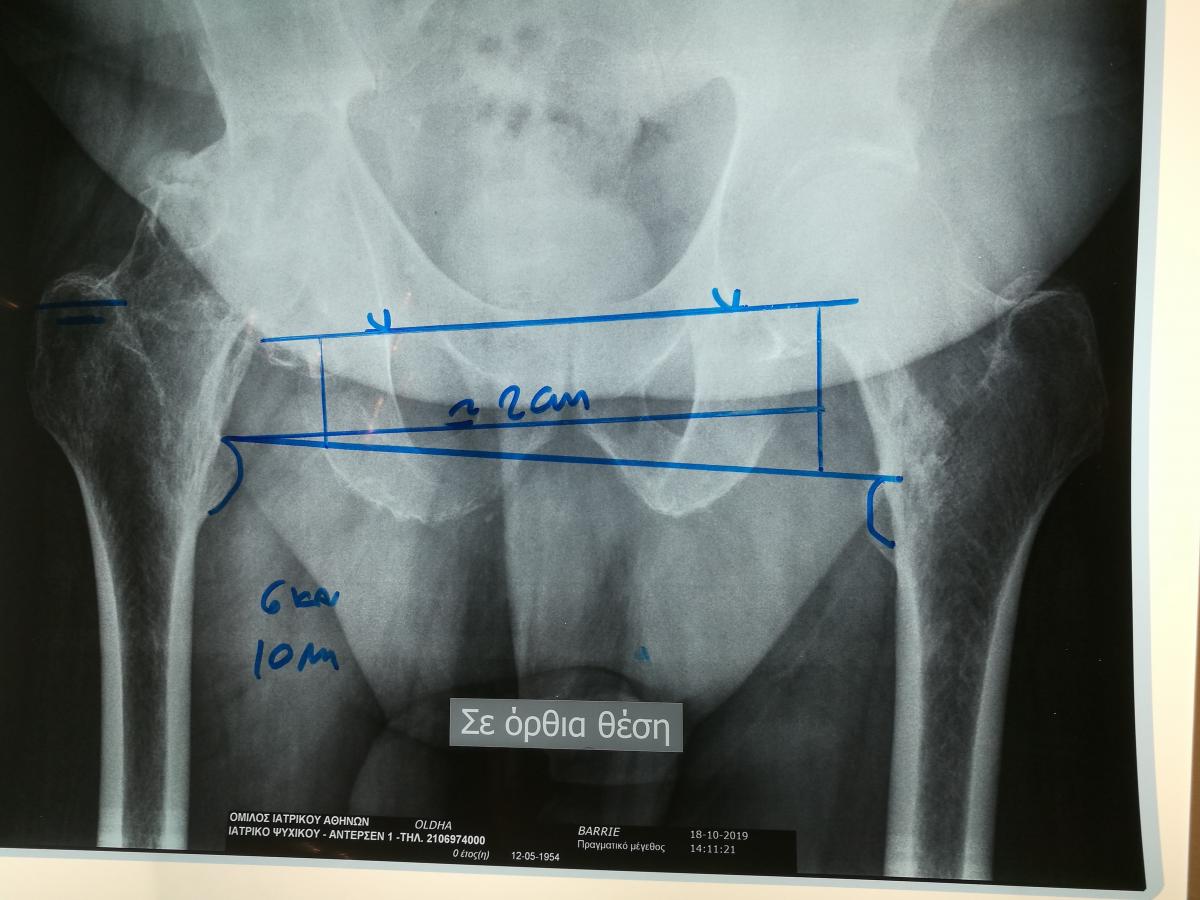

Компанія Lima надала стажування в ортопедичній приватній клініці місті Афіни Греція в листопаді 2019 року. Ендопротезування кульшового суглоба протезами компанії Lima малоінвазивним передньо-латеральний доступом у професора Христодулоса.